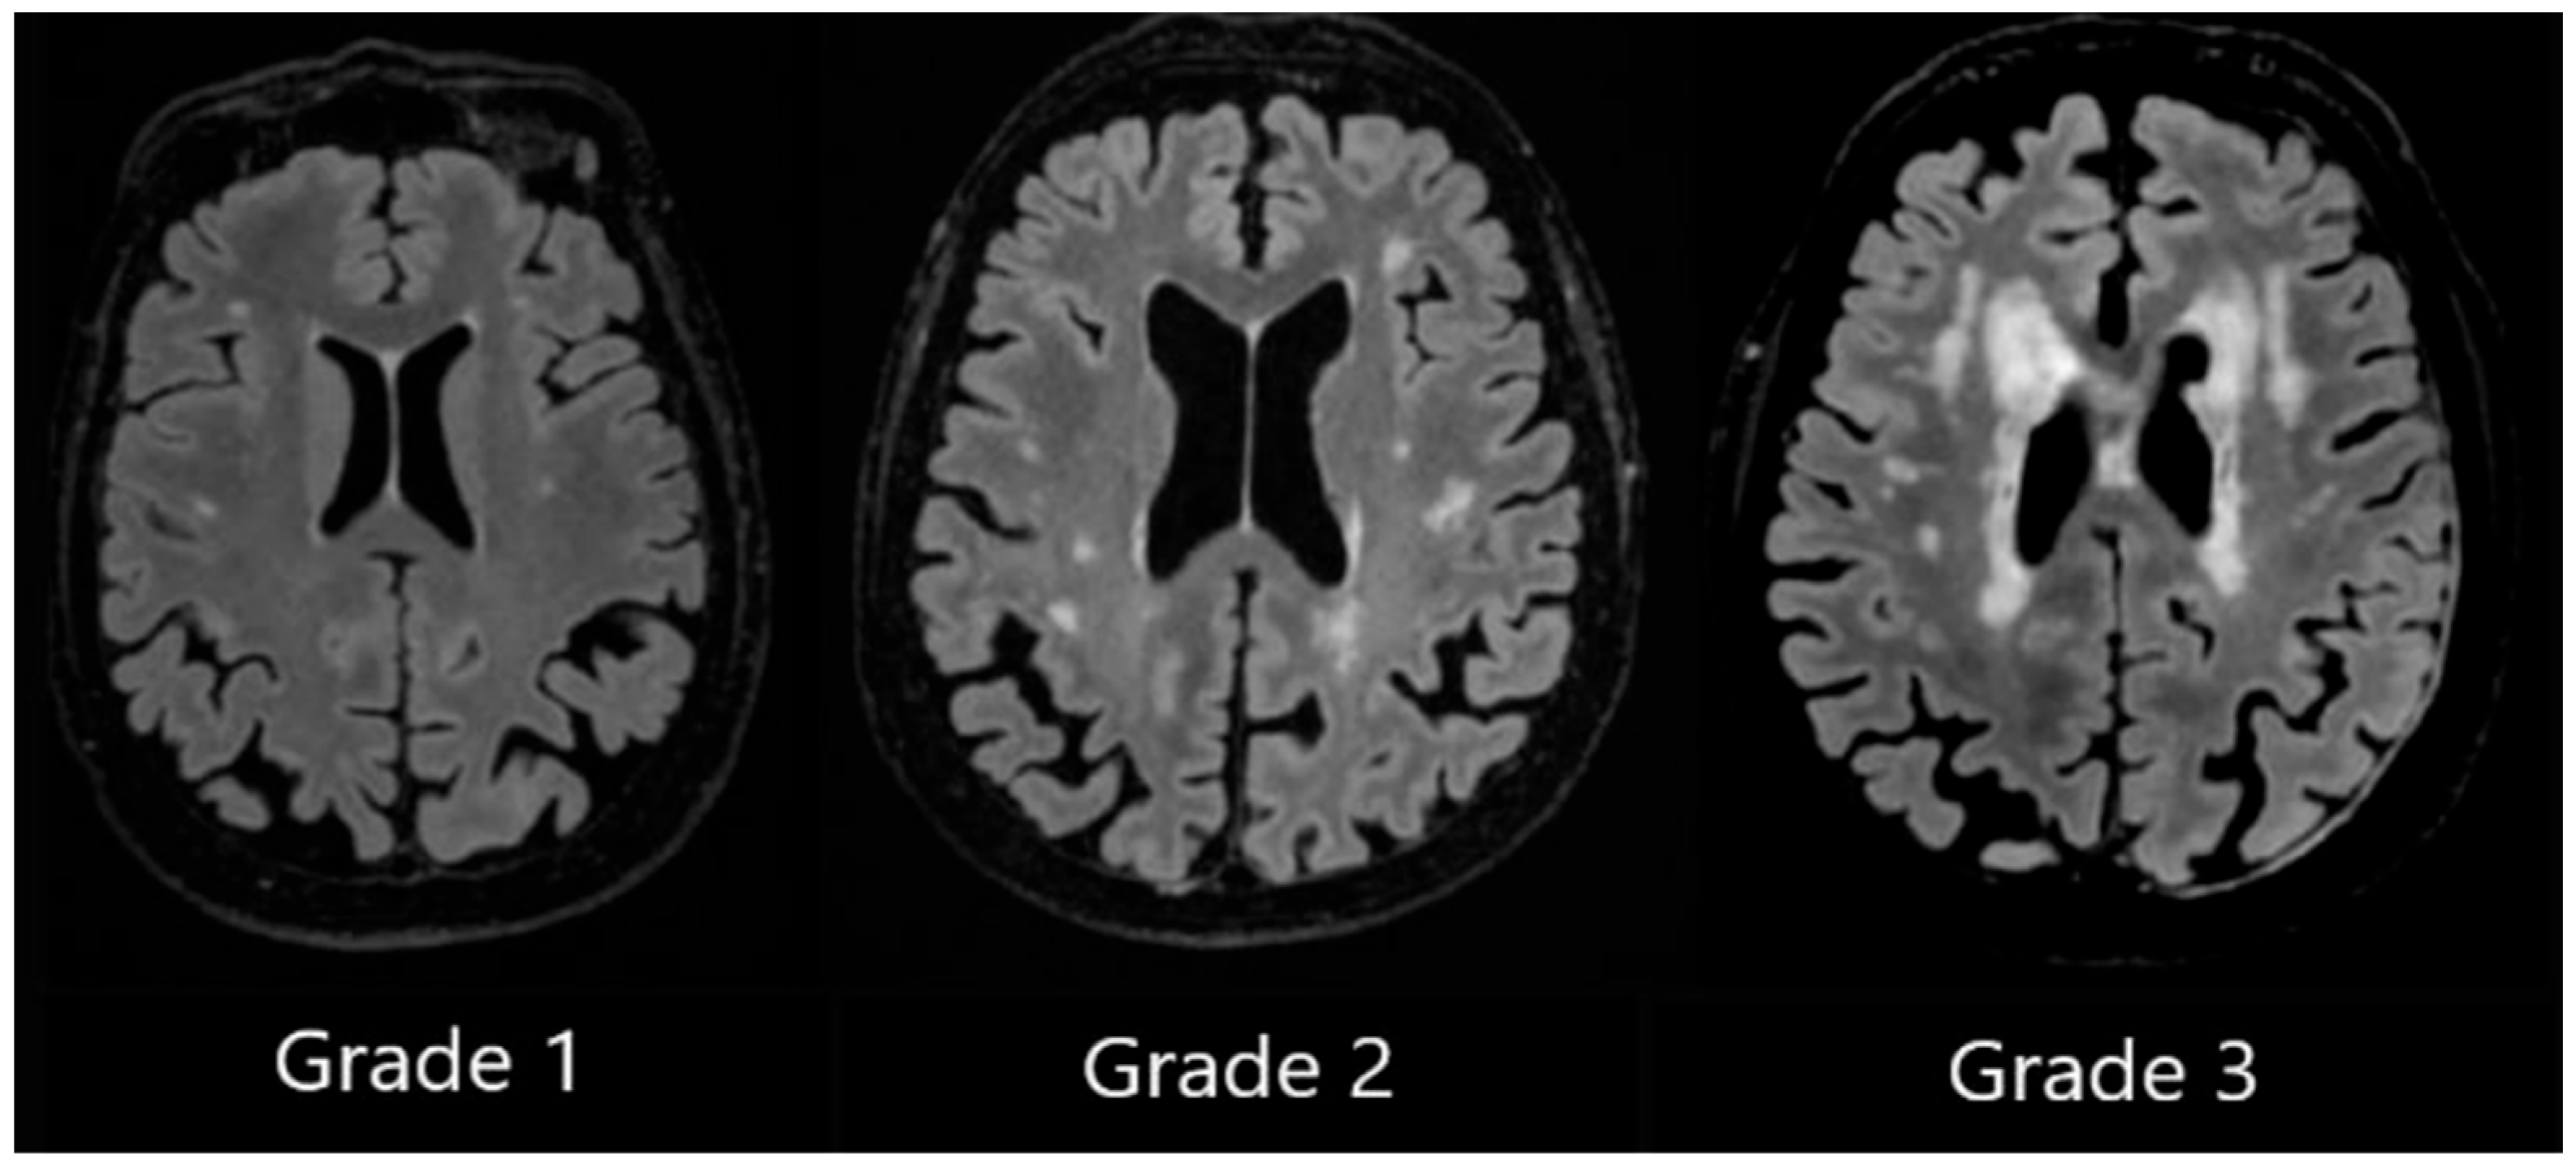

DWMH Grade 1 was assigned when small, punctate foci in subcortical regions were observed, Grade 2 was assigned to patients with a greater number of foci along with the early formation of white matter hyperintensity confluences, and Grade 3 was assigned to patients with large confluent areas of white matter hyperintensities (see Figure 2).

Figure 2. Deep white matter hyperintensities based on the Fazekas scale, ranging from Grade 1 to Grade 3, based on the severity of lesions.